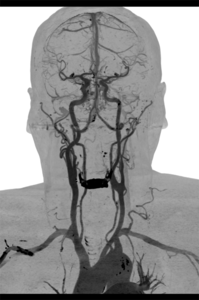

Die Gefäßdarstellung erfolgt in einem modernen 48-Kanal-Magnetresonanztomografen (Siemens Area 48) der mit spezieller Hard- und Software für die Darstellung aller Gefäße des Körpers ausgerüstet ist. Dazu wird überwiegend ein gadoliniumhaltiges Kontrastmittel verwendet, welches meist über eine Armvene injiziert wird. Die Untersuchung dauert ca. 10 – 20 Minuten.

Neben der Erfassung von Veränderungen des Gefäßdurchmessers zur Beurteilung der Durchblutungsstörung, liefert uns diese Untersuchungsform auch wichtige Information zum Aufbau der Gefäßwände, zum Beispiel bei entzündlichen Gefäßerkrankungen und zum Nachweis von durchblutungsgestörtem Gewebe.

Für Patienten die aufgrund von Erkrankungen kein Kontrastmittel verabreicht bekommen dürfen, besteht durch eine spezielle softwaregestützte Untersuchungsmethode die Möglichkeit, eine Angiografie der Beine auch ohne Kontrastmittelgabe durchzuführen.